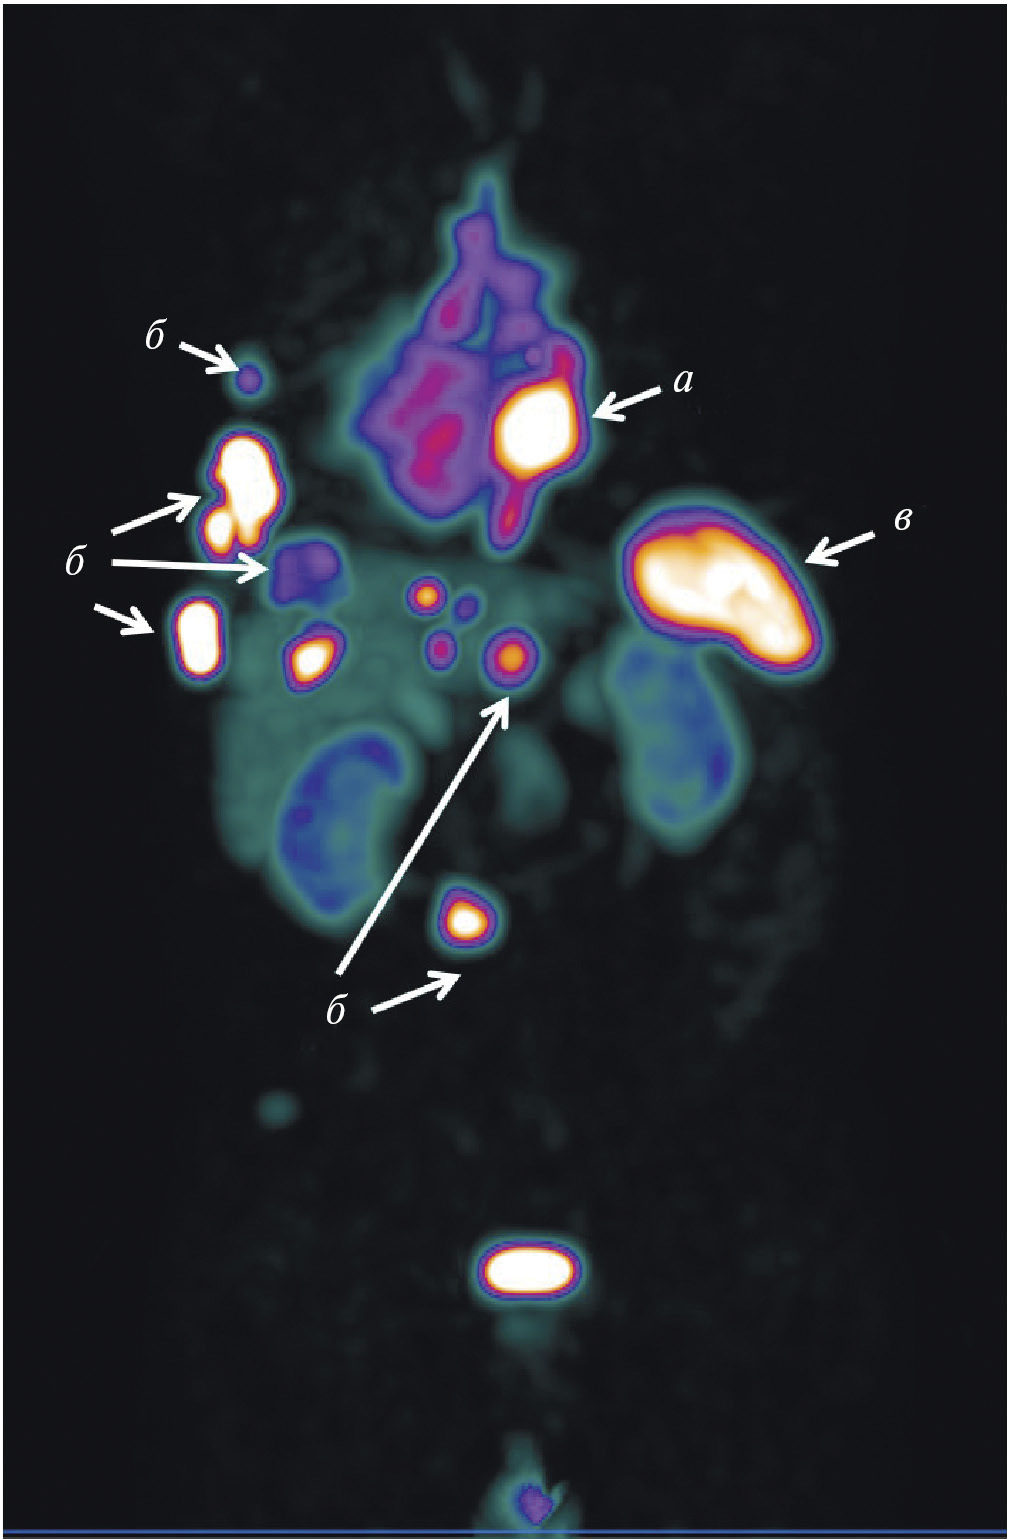

В НИИ онкологии Томского НИМЦ завершены первые фазы клинических исследований нескольких меченных технецием-99м каркасных белков (DARPin, ADAPT, Affibody), обладающих высокой аффинностью к рецептору эпидермального фактора роста второго типа (HER2/neu). Все препараты показали хорошую эффективность определения гиперэкспрессии рецептора HER2/neu при раке молочной железы и стадировании заболевания (рис. 1) [10, 11]. Кроме того, установлена возможность проведения ОФЭКТ/КТ с препаратами на базе скаффолдов для оценки эффекта терапии (рис. 2). Помимо основы РФЛП для диагностики злокачественных новообразований, каркасные белки могут служить вектором доставки при создании таргетных соединений для лечения злокачественных новообразований с гиперэкспрессией рецептора HER2/neu [13].

Рис. 1. ПЭТ-изображение пациентки с HER2/neu-позитивным раком молочной железы, выполненное через 5 суток после введения 89Zr-транстузумаба (a), стрелками обозначены метастазы в печень и кости [12]; ОФЭКТ-изображение пациентки с HER2/neu-позитивным раком молочной железы через 2 ч после введения 99mTc-ADAPT6 (б), стрелками обозначены первичная опухоль, метастазы в лимфатические узлы, печень и кости

Рис. 2. ОФЭКТ/КТ-изображение пациентки с HER2/neu-позитивным раком правой молочной железы до начала лечения, выполненное через 2 ч после введения 99mTc-DARPIN-G3 (а), стрелками обозначены первичная опухоль (SUVmax = 3.1), метастазы в лимфатические узлы (SUVmax = 8.8) и кости; ОФЭКТ/КТ-изображение той же пациентки после двух курсов терапии транстузумабом через 2 ч после введения 99mTc-DARPIN-G3 (б), стрелками обозначена первичная опухоль (SUVmax = 0.55), метастазы не визуализируются